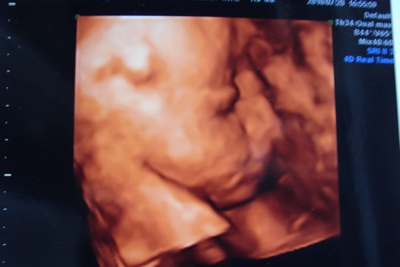

4D-s képek szuperek!!! Én is alig várom, hogy augusztus közepe legyen, akkorra tervezzük a menetelt, csak még bizonytalan vagyok, hogy hova is menjünk, mert a 4DGenesis-t nagyon sokan dicséritek, csak az nekünk elég messze van, vagy a másik lehetőség a Dr. Szöszi 4D, oda járok terhesgondozásra, viszont az uh-tól (12 hetest ott csinálták) és a szonográfustól nem voltam elájulva, mintha gyorsan túl akart volna lenni az egészen. De ha úgy fekszik, akár még jó képek is készülhetnek róla, viszont sajna nincsen csak egy alkalomra pénzünk, úgyhogy azt nem szeretném elszúrni....